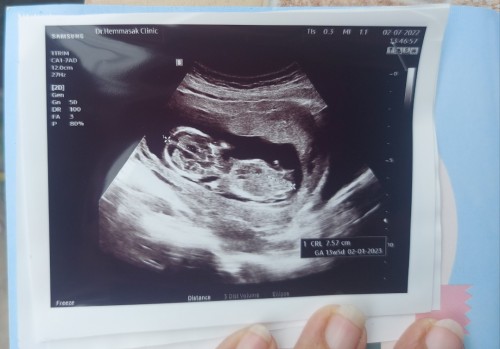

ขอดูตัวน้อยของแม่ไปทีมมกราคมหน่อยจ้า☺️☺️ อาการแม่ๆเป็นยังไงกันบ้างคะ บ้านนี้กินไม่ได้เลยกินนมก็ไม่ได้ออกทางเดิมตลอด🥺 #ทีมมกราคม 19 มกราคม 2566